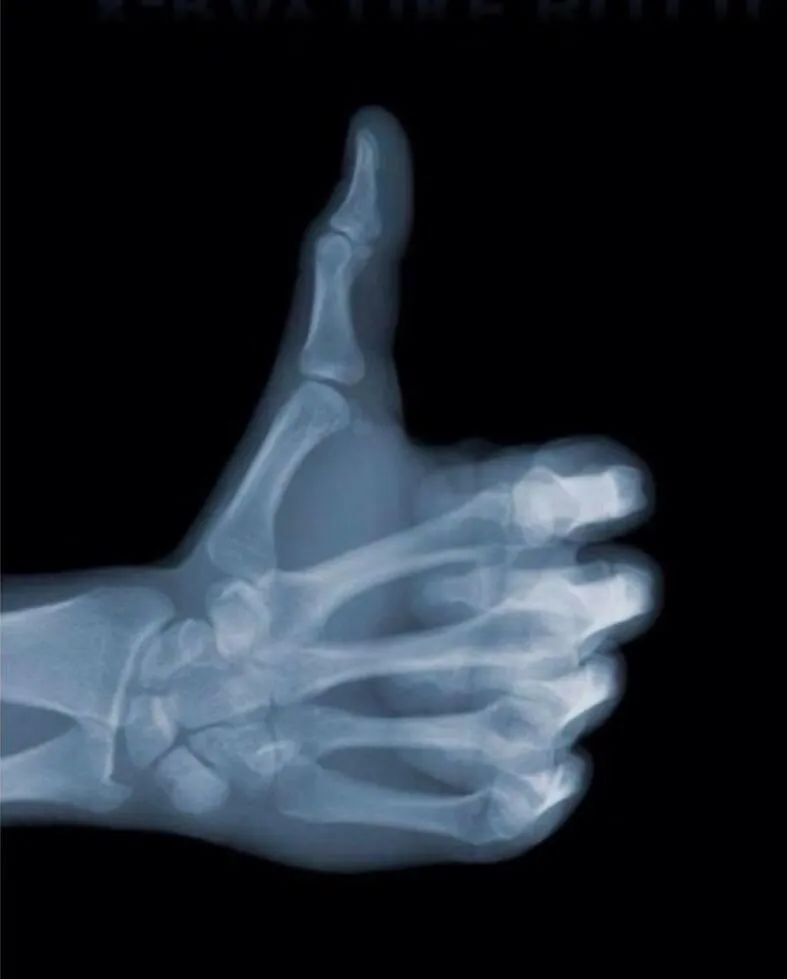

在生活中,读者对X射线有一定的了解。他们可能知道白色是骨头,而灰黑则是其他。

图片显示了一个在线表情套件包,源是未知的,但这看起来非常强大。

不同的组织和部分呈现不同的颜色,实际上与组织密度直接相关。组织密度越高,吸收X射线的越多,并且最终图像颜色越亮。因此,在X射线成像中,白色部分称为高密度,灰黑称为低密度。如果人体会导致损伤变化组织密度,则在达到一定水平后成像时将以黑色,白色和灰度变化。